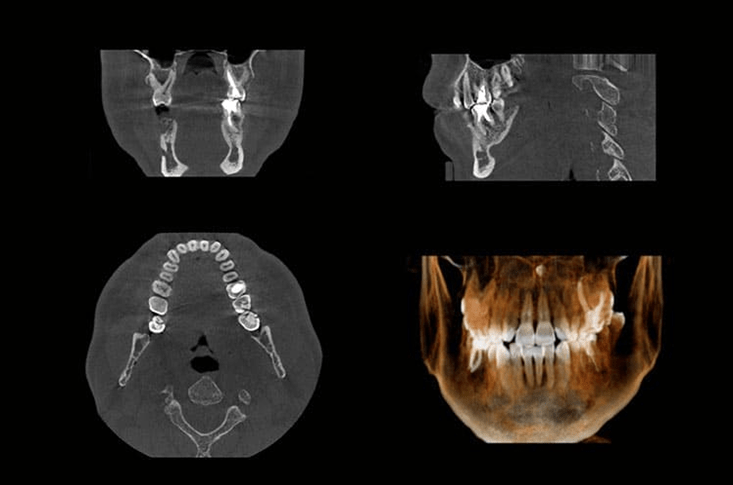

1. CBCT Dental Scan – See Every Detail Clearly

One of the most revolutionary tools in modern dentistry is the CBCT (Cone Beam Computed Tomography) scan. Unlike traditional X-rays, CBCT scans provide a detailed 3D view of your teeth, jaw, and surrounding structures.

- Highly detailed images for accurate diagnosis

- Better treatment planning for implants, orthodontics, and root canals

- Lower radiation exposure compared to older imaging methods

At V Dental Care in Vizag, Vizianagaram, and Srikakulam, CBCT is particularly valuable for planning affordable dental implants and other complex surgical procedures. By seeing every detail clearly, dentists can ensure precision-guided treatments that deliver long-lasting results.